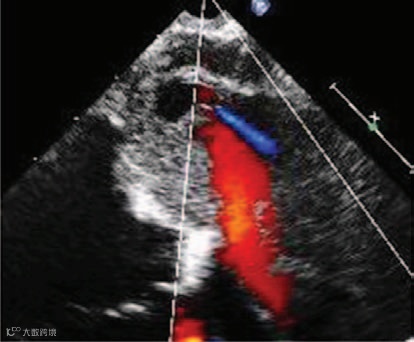

显示肿瘤内部有动态烟雾样回声(提示存在自发显影,图3;视频I)。M型超声显示肿瘤在收缩期两次回弹至左心房腔,产生M形信号(图4;视频II),提示肿瘤内部充满液体而非凝血,呈现血球样外观。彩色多普勒显示有血流流入(图5)和流出肿瘤(图6),且主要发生在舒张期(图7和8;视频III),提示血供来源于冠状动脉。

图5

图6